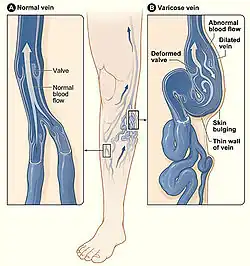

Varicose veins

Lower extremity varicose veins is the condition in which the superficial veins become tortuous (snakelike) and dilated (enlarged) to greater than 3 mm (0.12 in) in the upright position.[24] Incompetent or faulty valves are often present in these veins when investigated with duplex ultrasonography. Vascular treatments can include compression stockings, venous ablation or vein stripping, depending on specific patient presentation, severity of disease, among other things.